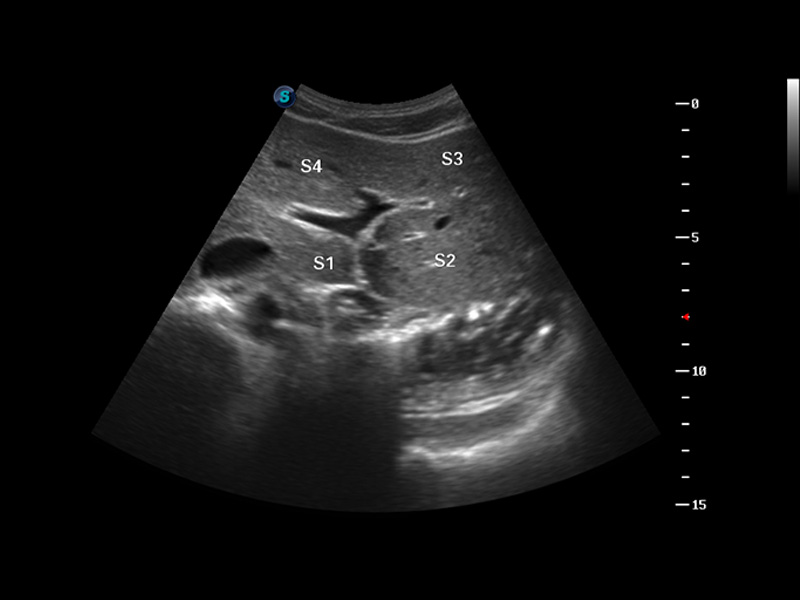

S8 EXP便携式彩色多普勒超声诊断仪是DB中国旗舰官方网站研发的高端全身应用型便携彩超。高通道的VIS平台融合可视化(Visual)、智能化(Intelligent)和人性化(Smart)的特点,配以DB中国旗舰官方网站自主研发生产的探头大家族,使您能够快速、准确的获得病人信息,提高工作效率的同时减轻疲劳。

成像技术

多波束形成器

μ-Scan微米成像

谐波成像

实时宽景成像

空间复合成像

3D/4D成像